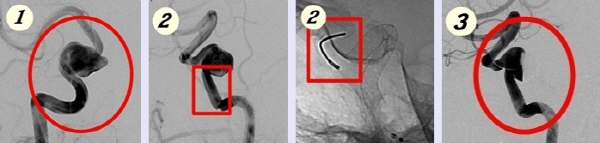

뇌동맥류는 현재 세계적으로 외과적인 수술요법_동맥류 결찰술과 혈관내수술 수술요법_뇌동맥류 코일 색전술을 병행해 수술하는데 이번에 진행된 최신 ‘파이프라인 스텐트 시술’은 스텐트 삽입으로 혈류의 방향을 전환 시켜 거대동맥류를 치료하는 시술이다. 국민일보 쿠키뉴스 김성지 기자 ohappy@kukimedia.co.kr

[사진설명= ①거대 뇌동맥류 ②파이프라인 스텐트를 뇌동맥에 삽입, 혈류 방향을 바꾸는 시술 시행 ③시술 30분 후 뇌동맥류 사이즈가 감소된 모습]